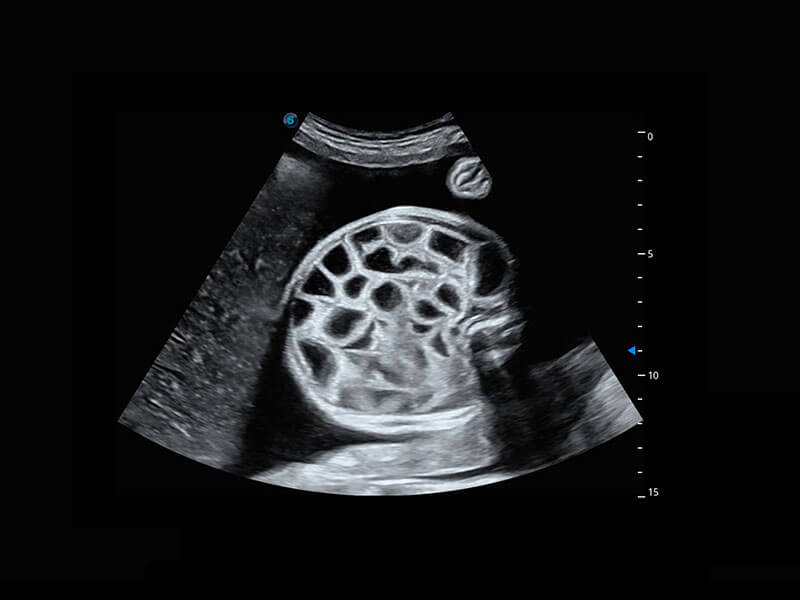

中晚孕筛查

P60提供简单易学易用的高端诊断工具,为您中晚孕筛查提供快速清晰的解剖信息。

基于Wis+平台内嵌的深度学习成果,S-Fetus能够助您在实时扫查过程中自动识别标准切面、自动测量并录入报告。一个按键,即可快速、高效地获取胎儿生理指标,简化您的产科检查操作。

S-Fetus(acq.)

& S-Fetus(meas.)

S-Fetus